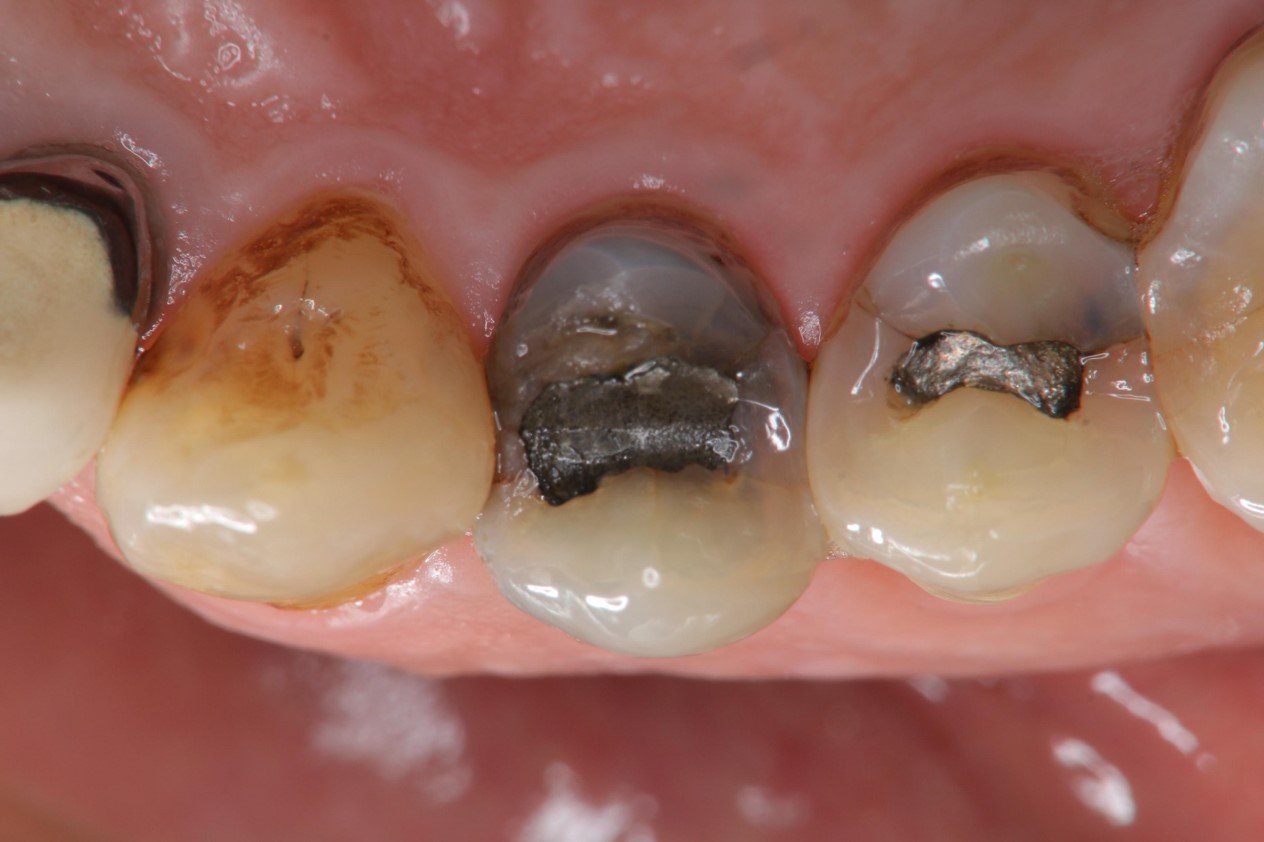

治療前,銀粉導致滲透

蛀牙未至牙髓